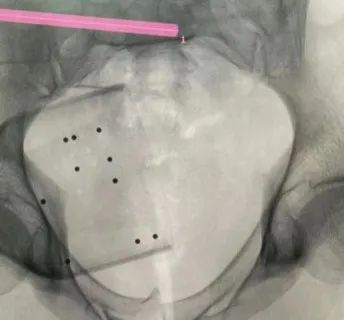

机器人完成患者信息二维图像采集后设计出螺钉置入方向

透视下见置入的骶髂螺钉,位置、长度精准,无丝毫偏差